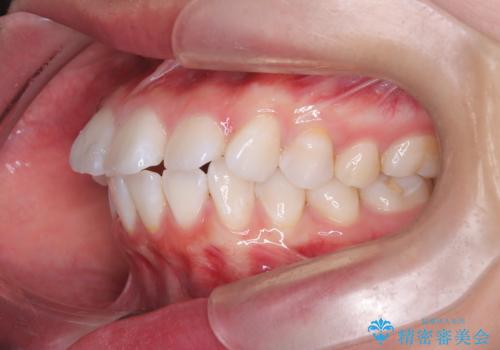

突き出た前歯を下げて理想的な横顔に。上下左右4番抜歯による審美ワイヤー矯正

精密検査の結果、歯を後方へ下げるためのスペースが不足していたため、上下左右の4番目の歯(第一小臼歯)を計4本抜歯する計画を立案しました。抜歯によってできたスペースを最大限に活用し、前歯を後ろに下げることで、口元のボリュームを抑え、バランスの良いEライン(横顔のライン)を目指すこととしました。装置は、日常生活で目立ちにくい審美ワイヤーを選択しました。

治療は、審美ワイヤーを用いて抜歯スペースを徐々に閉じながら、前歯の角度と位置を精密にコントロールして進められました。ワイヤー矯正は歯を三次元的にしっかりと動かすことができるため、前歯を単に倒すのではなく、根元から理想的な位置へと誘導しました。

1年半の治療期間を経て、抜歯したスペースは完全に閉じ、突き出ていた前歯はすっきりと内側に収まりました。噛み合わせの精度も向上し、機能面でも良好な結果が得られています。

治療完了後、口元の突出感が解消されたことでお顔全体の印象がシャープになり、患者様からも大変満足していただくことができました。目立ちにくい装置を使用したことで、1年半という期間も無理なく継続し、理想的なゴールを迎えることができました。